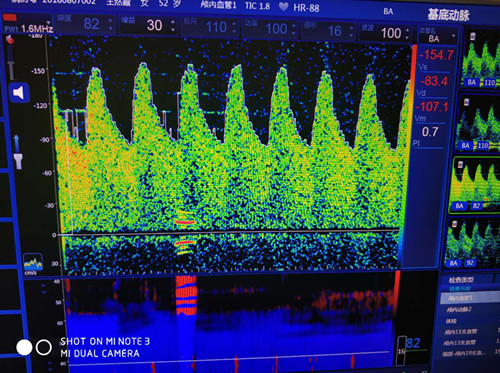

基底動(dòng)脈血流速度增高